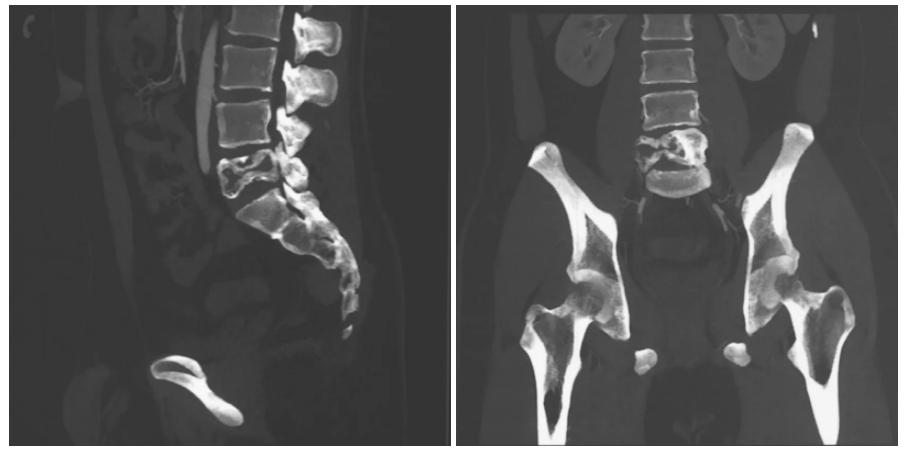

术前影像学检查

近日,空军军医大学唐都医院骨科郭征主任团队成功实施一例“腰5肿瘤切除-3D打印定制式人工椎体重建内固定术”,让患者重获健康。21岁的大四学生小贾即将完成大学学业、梦想踏入研究生学习,困扰他几个月的腰腿痛症状却越来越严重,到医院检查后确诊骨巨细胞瘤。骨巨细胞瘤一种交界性肿瘤,有恶性的生长潜能,手术切除是其主要的治疗方式,但是肿瘤局部复发率高,同时存在转移恶变可能。尤其腰椎骨巨细胞瘤毗邻重要的血管神经,完整切除困难,手术风险高。此外,肿瘤切除后的脊柱结构重建也是一大挑战。

目前临床传统使用的钛网重建虽然即刻稳定性尚可,但由于解剖匹配性差、骨整合不良、应力集中等缺陷,假体长期稳定性差,下沉、移位等假体相关并发症多,多数患者需面临再次手术翻修的可能,小贾的人生瞬间布满阴霾。